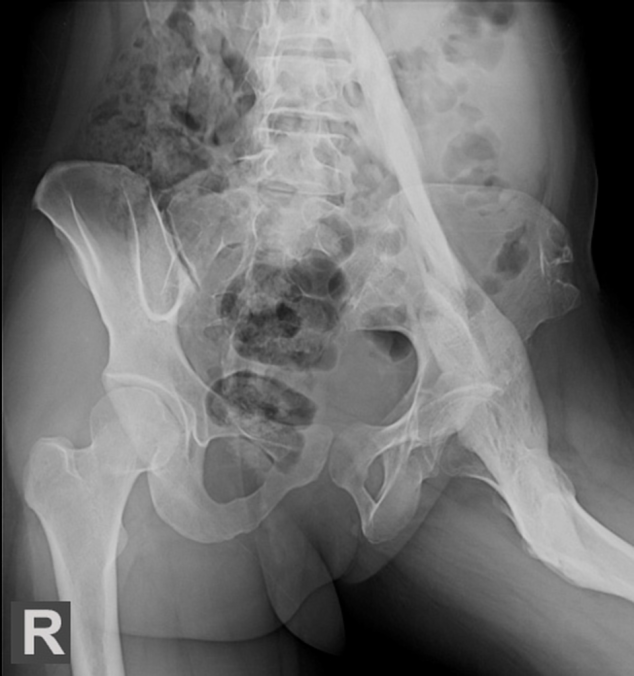

Osteopetrosis

diffuse marked sclerosis of the entire skeleton

sandwich sign

spine sign in osteopetrosis